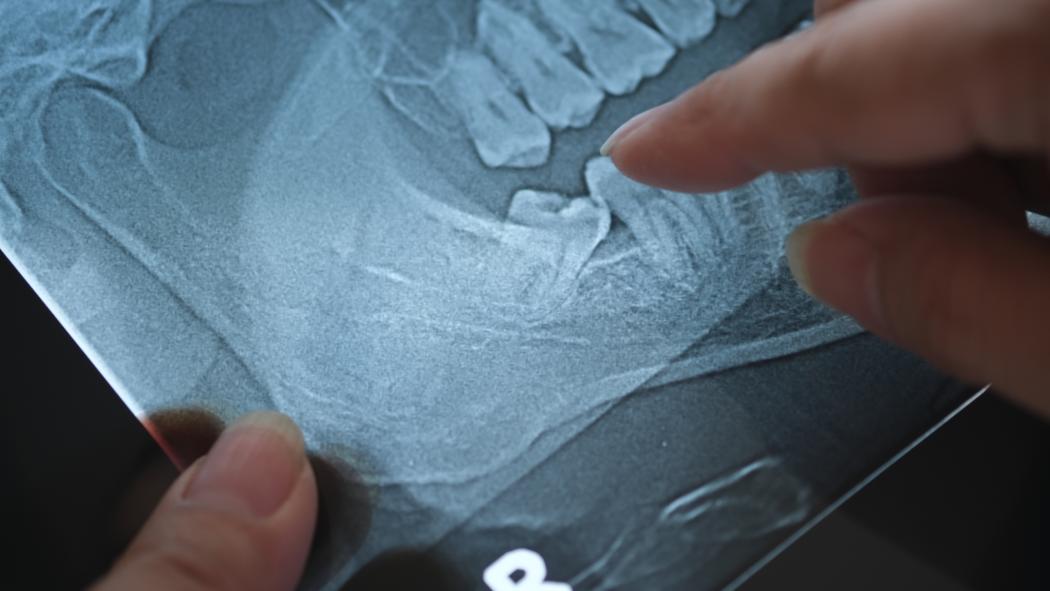

So, does candy really cause tooth decay? The answer to this question is a little more complicated than you might think. The candy itself does not actually cause tooth decay, but it certainly contributes to the problem. Tooth decay is caused by acid-producing bacteria in your mouth that feast on carbohydrates. These carbohydrates can come in the form of candy or even starchy foods like bread. The longer these foods remain on the surface of your teeth, the more likely they are to feed the harmful bacteria that cause tooth decay. For this reason, certain candies and foods are more likely to cause tooth decay than others. That’s right, when it comes to tooth decay, not all candies are alike.

If you are worried about tooth decay in your children, you will want to limit their intake of candies and foods that stick to the surface of and in between the teeth. You know the kind: gummy worms, licorice and even fruit rollups. If they do enjoy these types of treats, it is important to limit the amount of time that the sugar stays on the surface of their teeth. You can limit their exposure by having them rinse with water after eating sugary foods. Even better, you can have them brush and floss their teeth after eating candy.